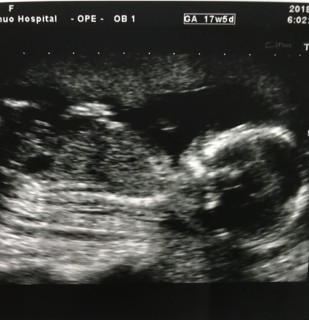

写真:17w5d:かおちさん

17週5日に3回目の検診に行ってきました。赤ちゃんもとても元気でした!!

性別は分からないな〜とのこと

検診の時の赤ちゃんの体重身長は

体重160g

身長15cm

と平均身長体重よりも少し大きいらしいです!!良かった♡